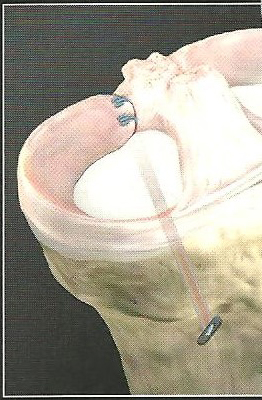

Η μεταμόσχευση του μηνίσκου, από πτωματικά φρέσκα κατεψυγμένα μοσχεύματα, παραμένει μέχρι και σήμερα ένα αντικείμενο συζήτησης χωρίς ξεκάθαρο συμπέρασμα. Από την πρώτη μεταμόσχευση που ανακοίνωσε ο Milachkowski το 1984 ακολούθησαν μεγάλες σειρές αποτελεσμάτων από διάφορα Κέντρα παγκοσμίως, με περίοδο παρακολούθησης περισσότερο από 20 χρόνια από τις οποίες, παρά τις τεχνικές βελτιώσεις, δεν προκύπτει ούτε μόνιμο και μακροχρόνιο όφελος για τον ασθενή, ούτε καθυστέρηση στην εμφάνιση οστεοαρθρίτιδος και παραμένουν ασαφείς οι ενδείξεις όσον αφορά στην ηλικία του ασθενούς, τον κατάλληλο χρόνο μεταμόσχευσης, τη χαμηλή αποτελεσματικότητα σε σχέση με το κόστος (cost effectiveness), κ.ά. (εικόνα 6).